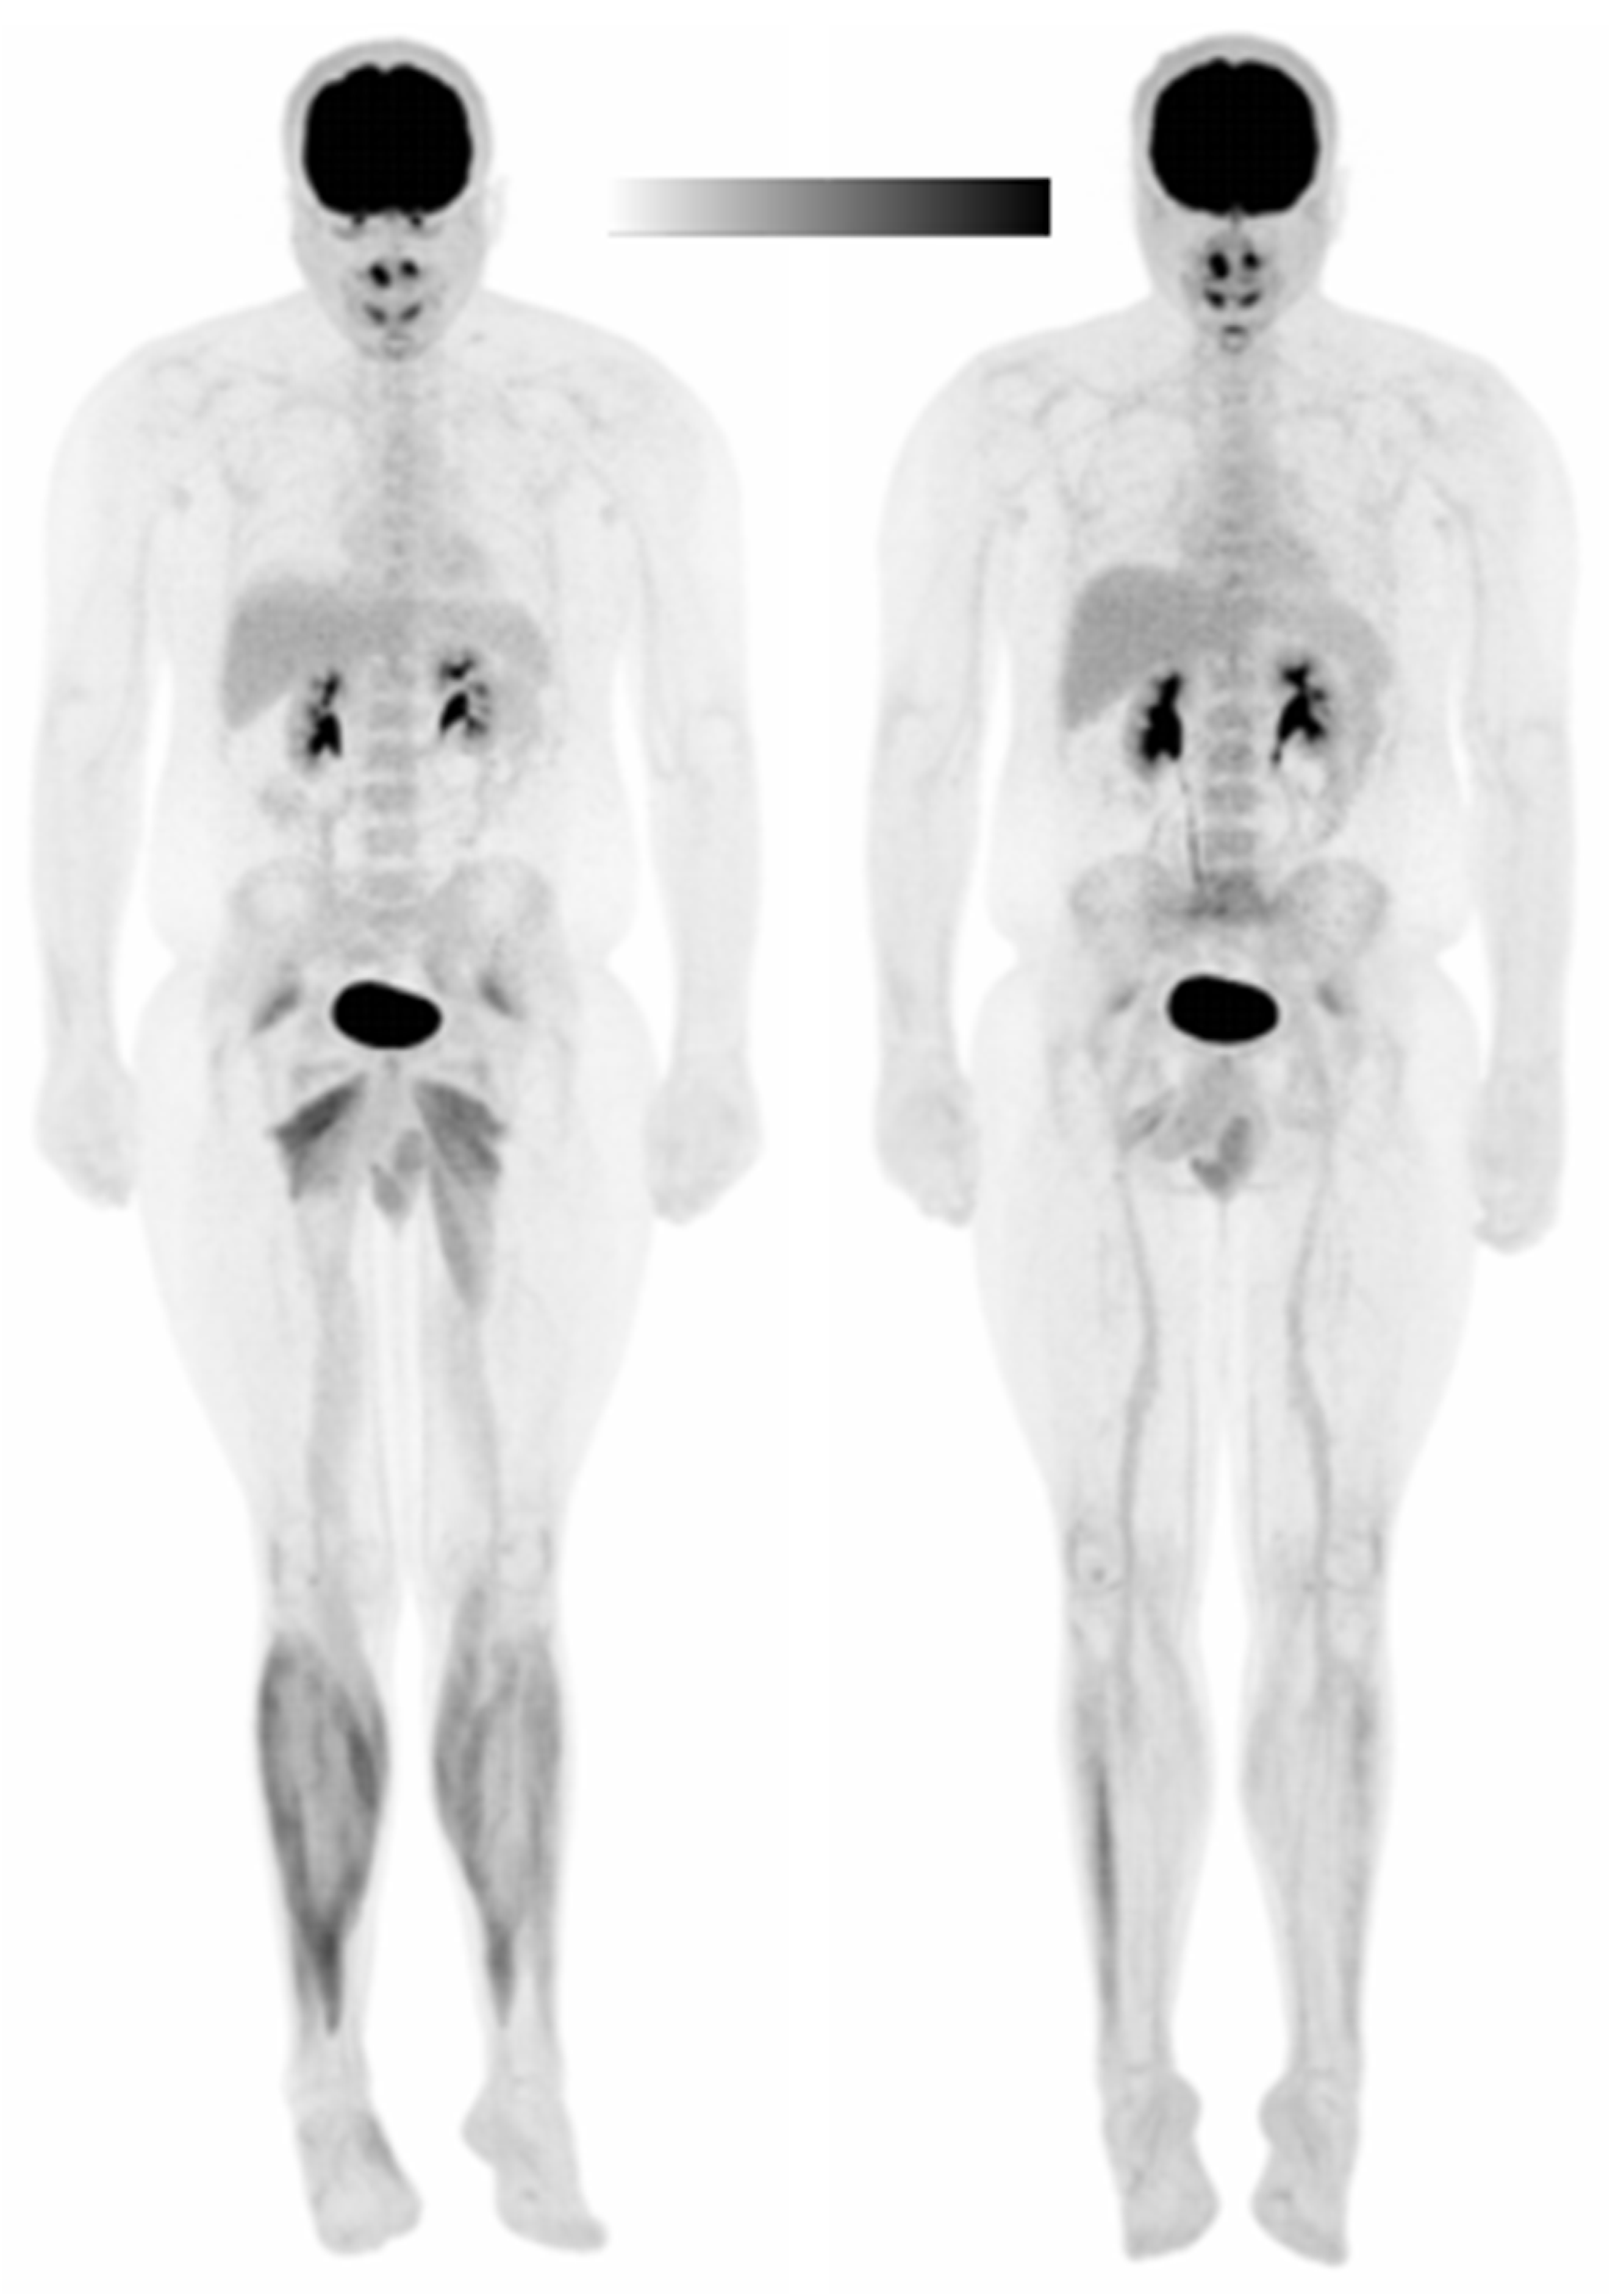

3. Results

3.1. Subject 1

3.1.1. Standardized Uptake Values (SUVs)

3.1.2. Asymmetry Indices (AIs)

3.1.3. Glucose Uptake Heterogeneity (GUh)

3.2. Subject 2

3.2.1. Standardized Uptake Values (SUVs)

3.2.2. Asymmetry Indices (AIs)

3.2.3. Glucose Uptake Heterogeneity (GUh)

3.3. Subject 3

3.3.1. Standardized Uptake Values (SUVs)

3.3.2. Asymmetry Indices (AIs)

3.3.3. Glucose Uptake Heterogeneity (GUh)

3.4. Subject 4

3.4.1. Standardized Uptake Values (SUVs)

3.4.2. Asymmetry Indices (AIs)

3.4.3. Glucose Uptake Heterogeneity (GUh)